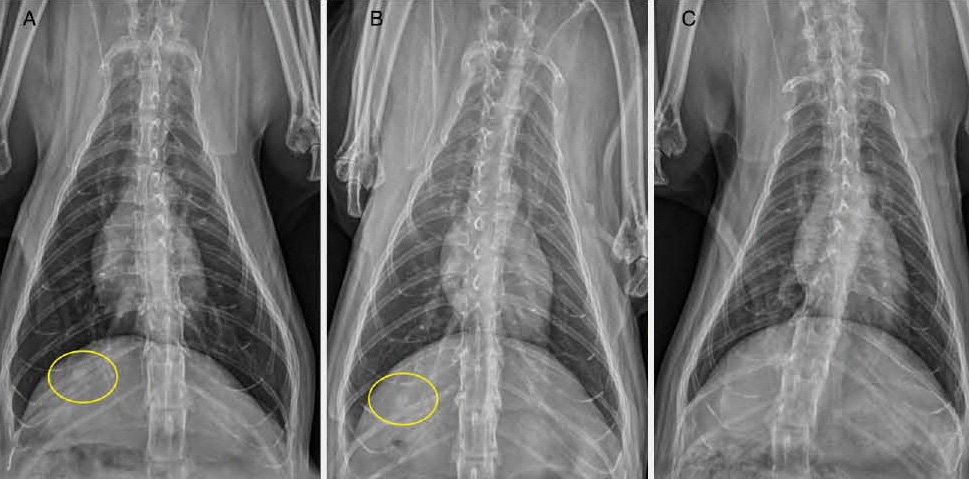

写真3はこのパイロット研究の猫の鼻腔内腺癌から肺転移がみられた症例のX線像です(論文から転用)。鼻腔内の腫瘍病変が放射線治療で部分寛解した後に肺転移が認められ、肺転移病巣に対して放射線治療を行い、直径約5mmの肺転移巣が縮小、そして消失しました。その過程、結果は胸部CT検査でも確認しました。